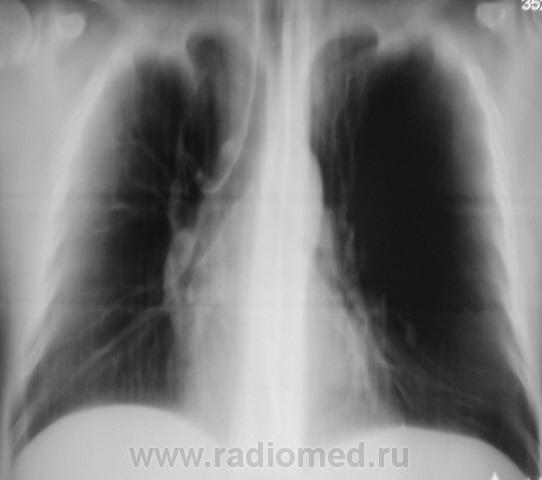

Флюорограмма.

Рентгенограмма в прямой проекции.